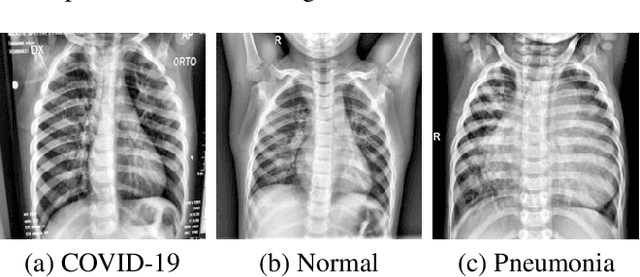

Abstract:Coronavirus Disease 2019 (COVID-19) demonstrated the need for accurate and fast diagnosis methods for emergent viral diseases. Soon after the emergence of COVID-19, medical practitioners used X-ray and computed tomography (CT) images of patients' lungs to detect COVID-19. Machine learning methods are capable of improving the identification accuracy of COVID-19 in X-ray and CT images, delivering near real-time results, while alleviating the burden on medical practitioners. In this work, we demonstrate the efficacy of a support vector machine (SVM) classifier, trained with a combination of deep convolutional and handcrafted features extracted from X-ray chest scans. We use this combination of features to discriminate between healthy, common pneumonia, and COVID-19 patients. The performance of the combined feature approach is compared with a standard convolutional neural network (CNN) and the SVM trained with handcrafted features. We find that combining the features in our novel framework improves the performance of the classification task compared to the independent application of convolutional and handcrafted features. Specifically, we achieve an accuracy of 0.988 in the classification task with our combined approach compared to 0.963 and 0.983 accuracy for the handcrafted features with SVM and CNN respectively.